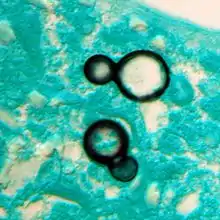

Once suspected, the diagnosis of blastomycosis can usually be confirmed by demonstration of the characteristic broad based budding organisms in sputum or tissues by KOH prep, cytology, or histology.[16] Tissue biopsy of skin or other organs may be required in order to diagnose extra-pulmonary disease. Blastomycosis is histologically associated with granulomatous nodules. Commercially available urine antigen testing appears to be quite sensitive in suggesting the diagnosis in cases where the organism is not readily detected. While culture of the organism remains the definitive diagnostic standard, its slow growing nature can lead to delays in treatment of up to several weeks. However, sometimes blood and sputum cultures may not detect blastomycosis.[17]

Large yeast-like fungi seen within giant cells at arrows.Budding yeasts in cytoplasm of giant cells at arrows. Broad-based budding and double contoured cell wall seen in the giant cell in the center is characteristic of Blastomyces dermatitidis.